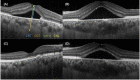

Methods: We divided 59 patients into non-prolonged (<3 months) and prolonged (>3 months) groups based on SRF fluid persistence from the initial visit. The follow-up period varied as the shorter duration was chosen between SRF disappearance time and 3 months from the initial visit. We measured the central retinal thickness (CRT), central choroidal thickness (CCT), SRF height (SRFH), and outer nuclear layer thickness (ONL) using spectral-domain optical coherence tomography (SD-OCT) at the initial visit and recorded SRF duration. We compared these parameters between the groups, conducted multivariate analysis for SRF duration of more than 3 months, and investigated the correlation among CCT and CRT, SRFH, or ONL, and among SRF duration and CRT, CCT, SRFH, or ONL.

Results: CCT was significantly thicker in the prolonged than in the non-prolonged group at the initial visit (P = 0.044) and significantly correlated with CRT and SRFH (P = 0.007, r = 0.35 and P = 0.002, r = 0.39). SRF duration significantly correlated with CRT and SRFH (P = 0.009, r = 0.40 and P = 0.003, r = 0.41). The optimal model for SRF duration more than 3 months included age (P = 0.054) and CCT (P = 0.008).